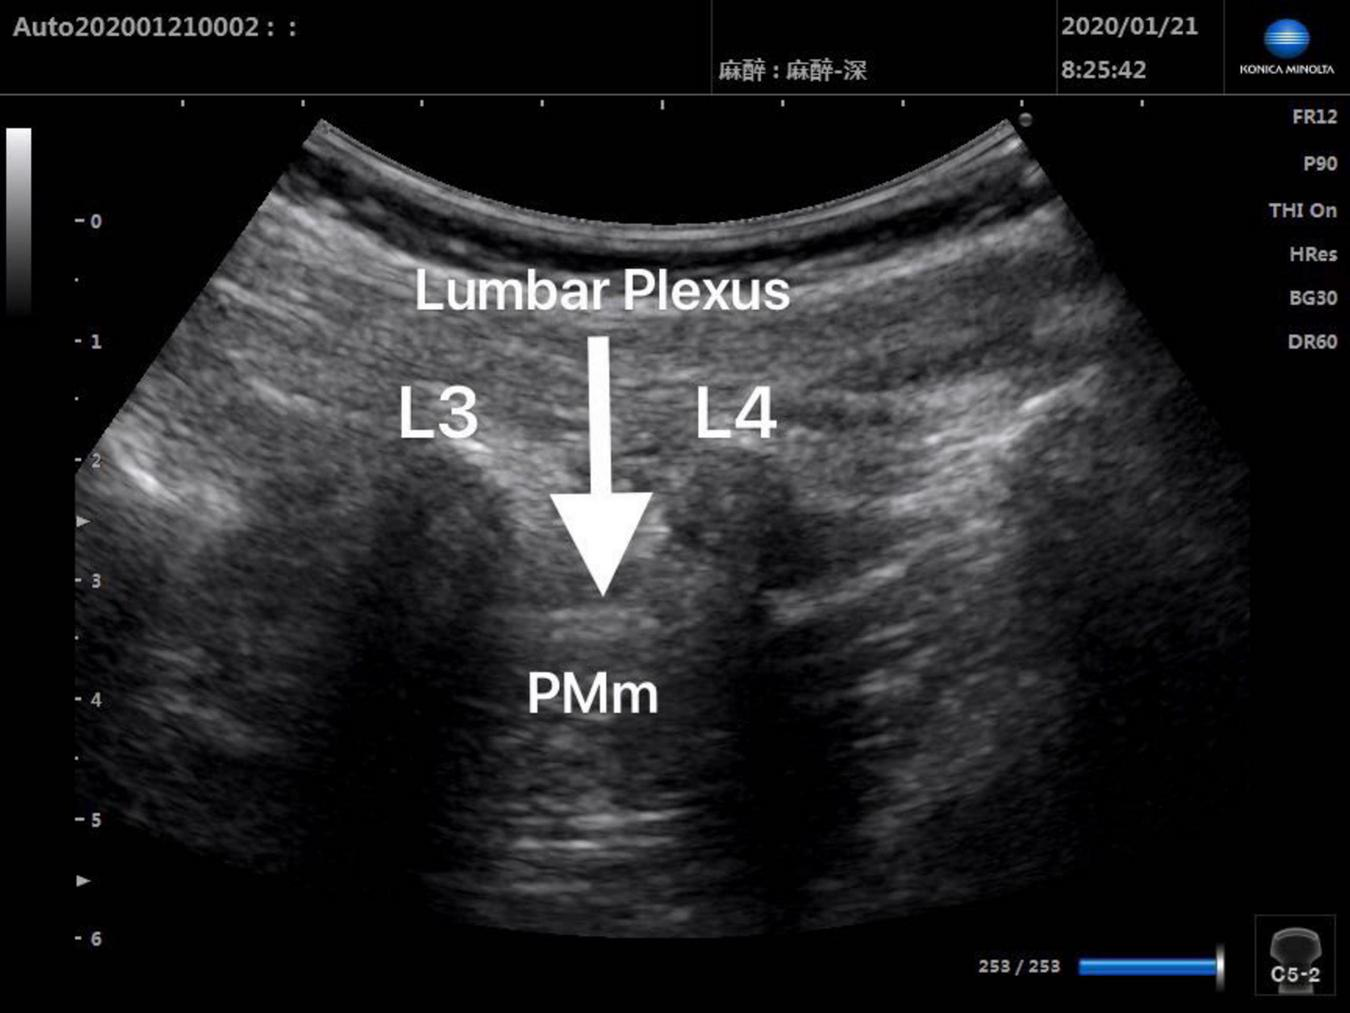

Patients in Group Block received ultrasound-guided lumbar plexus block before skin incision. Ultrasound scans of lumbar plexus were carried out using the S-NerveTM Ultrasound System (Sonosite Inc., Bothell, WA, United States) in patients assigned to Group Block. A linear array (6∼13 MHz) transducer was used to perform lumbar plexus block with the longitudinal approach. All nerve blocks in this study were performed by the same experienced anesthesiologist, who was qualified for ultrasound-guided lumbar plexus block. After induction, every patient assigned to Group Block was placed in the lateral decubitus position with the operative side upwards and the hips and knees flexed in order to enlarge interspinous spaces and provide better image of lumbar plexus. When transducer was placed 1.5∼2 cm lateral to the midline of the patient’s back and parallel to the long axis of the spine at the level L3-4, the lumbar transverse processes produced a “trident sign” (15). Because the psoas major muscle is anterior to the transverse processes, the lumbar plexus was distinguished within the major psoas muscle (Figures 1, 2). With ultrasound guidance, the block needle was advanced cautiously perpendicular to the skin until the needle tip was located 1–1.5 cm below the space between the transverse processes. All patients received 0.2% ropivacaine 1 ml/kg (Naropin 10 mg/ml, Astrazeneca, Wilmington, DE, United States) (16). The maximum dose of ropivacaine was limited to 20 ml (16).

FIGURE 1

Preinjection ultrasound image of L3-4 lumbar plexus block.